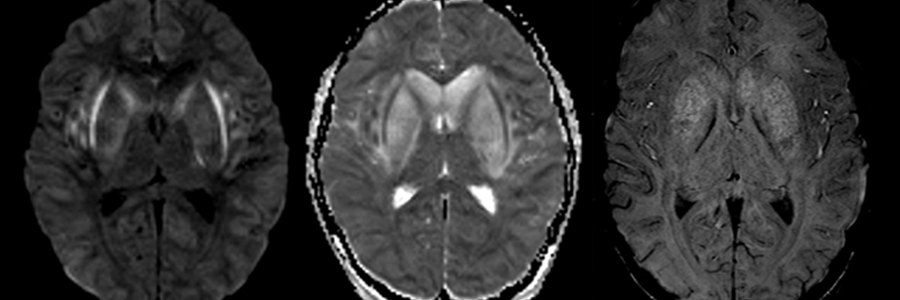

Caso 1 | Abril 2026 | Instituto Oulton Motivo de consulta: cuadro progresivo de desorientación, apatía, bradipsiquia y disartria, seguido de un episodio de pérdida de conocimiento.